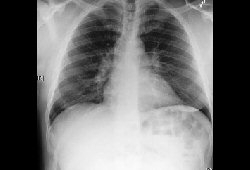

A radiografia torácica pode apresentar sinais de tuberculose miliar, câncer pulmonar ou sarcoidose.[Figure caption and citation for the preceding image starts]: Adenopatia hilar bilateral associada a sarcoidoseDo acervo de Muthiah P. Muthiah, MD, FCCP [Citation ends].